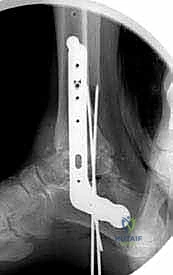

- Finally, use the guide pins to place a 6.5or 7.3-mm cannulated cancellous screw from the posterior tibia into the head of the talus to increase rigid fixation and further control rotation and from the anterior tibia into the tuberosity of the calcaneus ( TECH FIG 6 ).

Calcaneus A TECH FIG 6

- A. Blade plate and screw fixation construct for tibiocalcaneal arthrodesis. (continued)

TECH FIG 6 • (continued) B–D. Postoperative radiographs of tibiocalcaneal arthrodesis. B. Lateral view. C. AP view. D. Mortise view. E, F. Sawbones model with blade plate in optimal position.